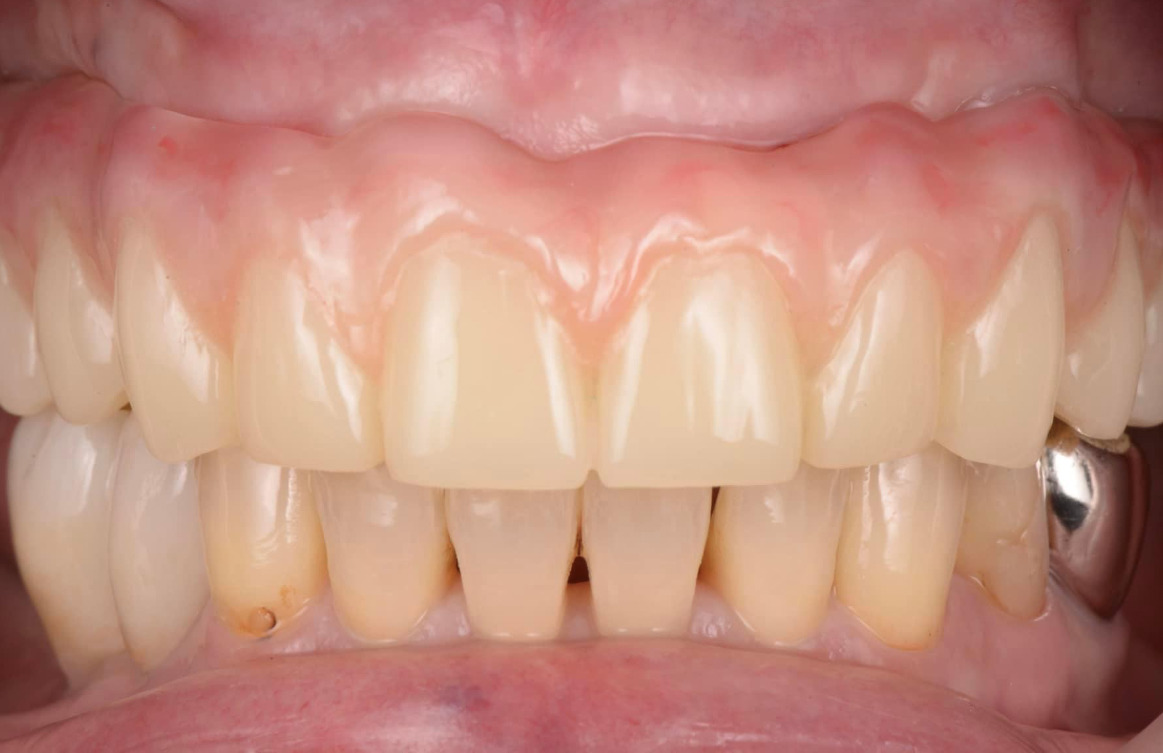

術前レントゲン、術後レントゲン。ジルコニアの単冠×4本の写真です。